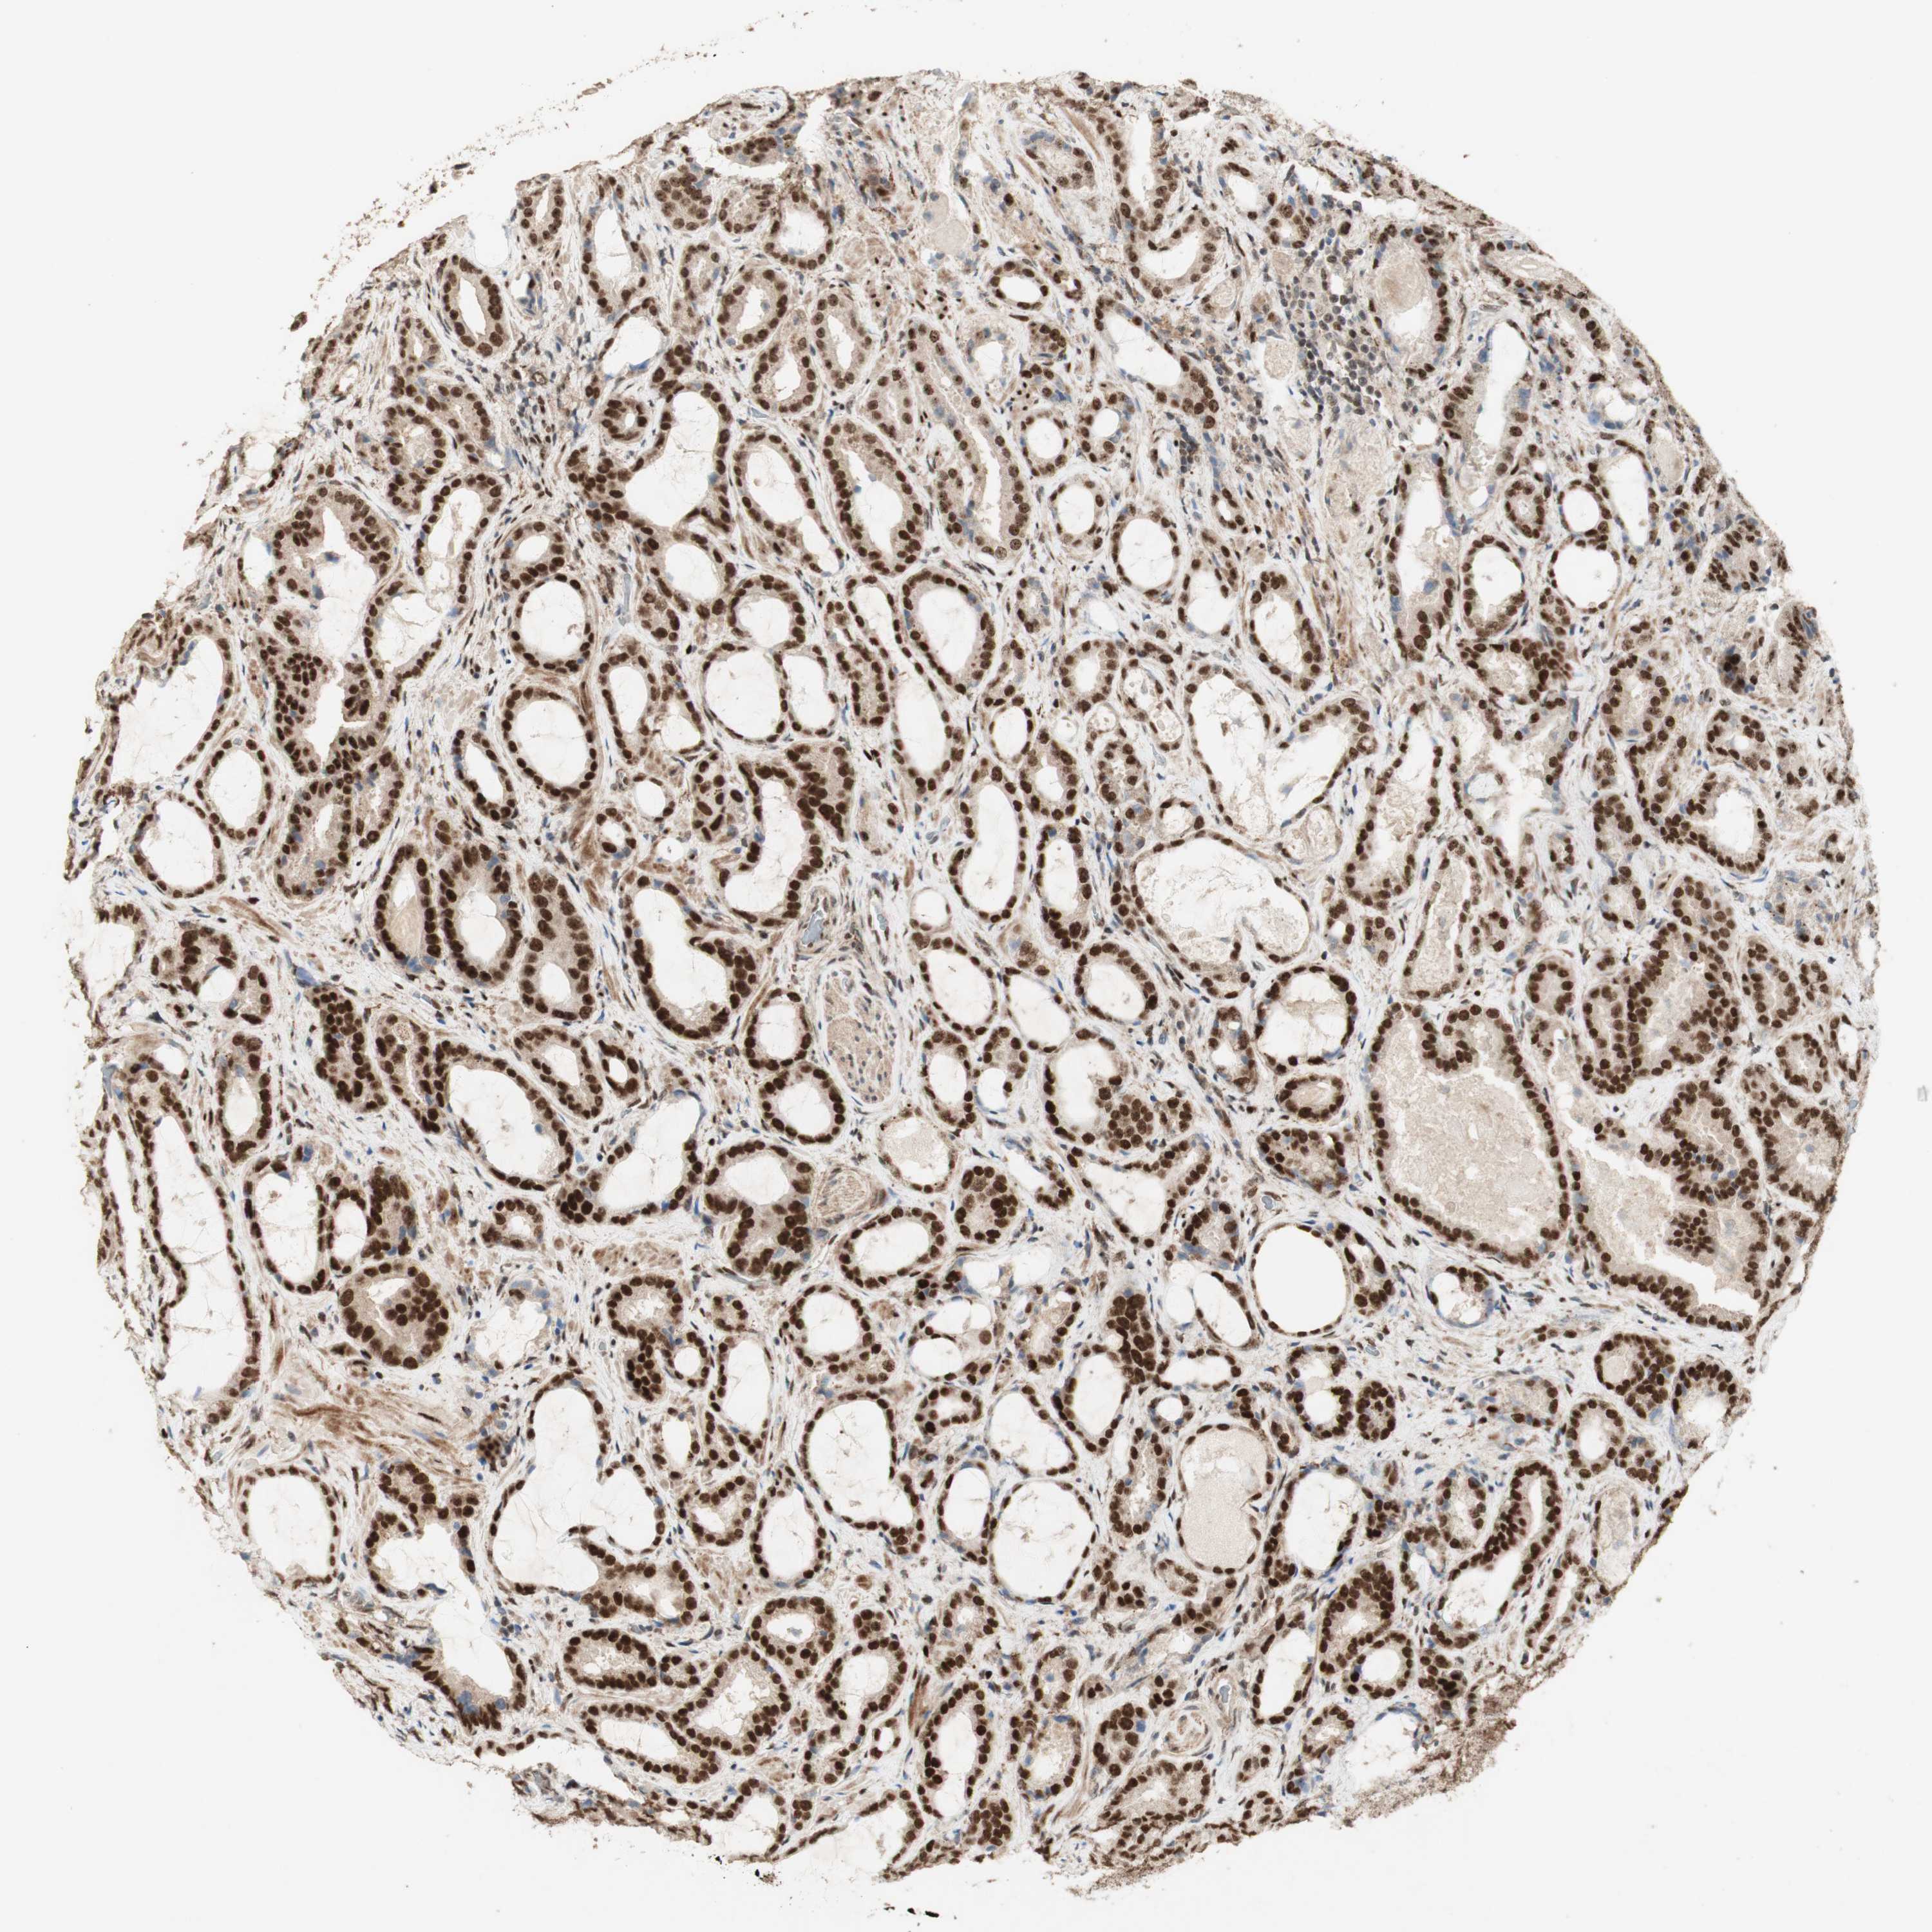

PROSTATE CANCER - Protein expressioni

A mouse-over function shows sample information and annotation data. Click on an image to view it in a full screen mode. Samples can be filtered based on level of antibody staining by selecting one or several of the following categories: high, medium, low and not detected. The assay and annotation is described here.

Antibody stainingi

Antibody staining in the annotated cell types in the current human tissue is reported as not detected, low, medium, or high, based on conventional immunohistochemistry profiling in selected tissues. This score is based on the combination of the staining intensity and fraction of stained cells.

Each image is clickable and will lead to virtual microscopy that enables deeper exploration of all samples and also displays staining intensity scores, fraction scores and subcellular localization as well as patient and tissue information for each sample.

Antibody HPA003876

Antibody CAB011501

Staining

High

Medium

Low

Not detected

Intensity

Strong

Moderate

Weak

Negative

Quantity

>75%

75%-25%

<25%

None

Location

Nuclear

Cytoplasmic/membranous

Cytoplasmic/membranous,nuclear

Adenocarcinoma, Low grade

Adenocarcinoma, Medium grade

Adenocarcinoma, High grade